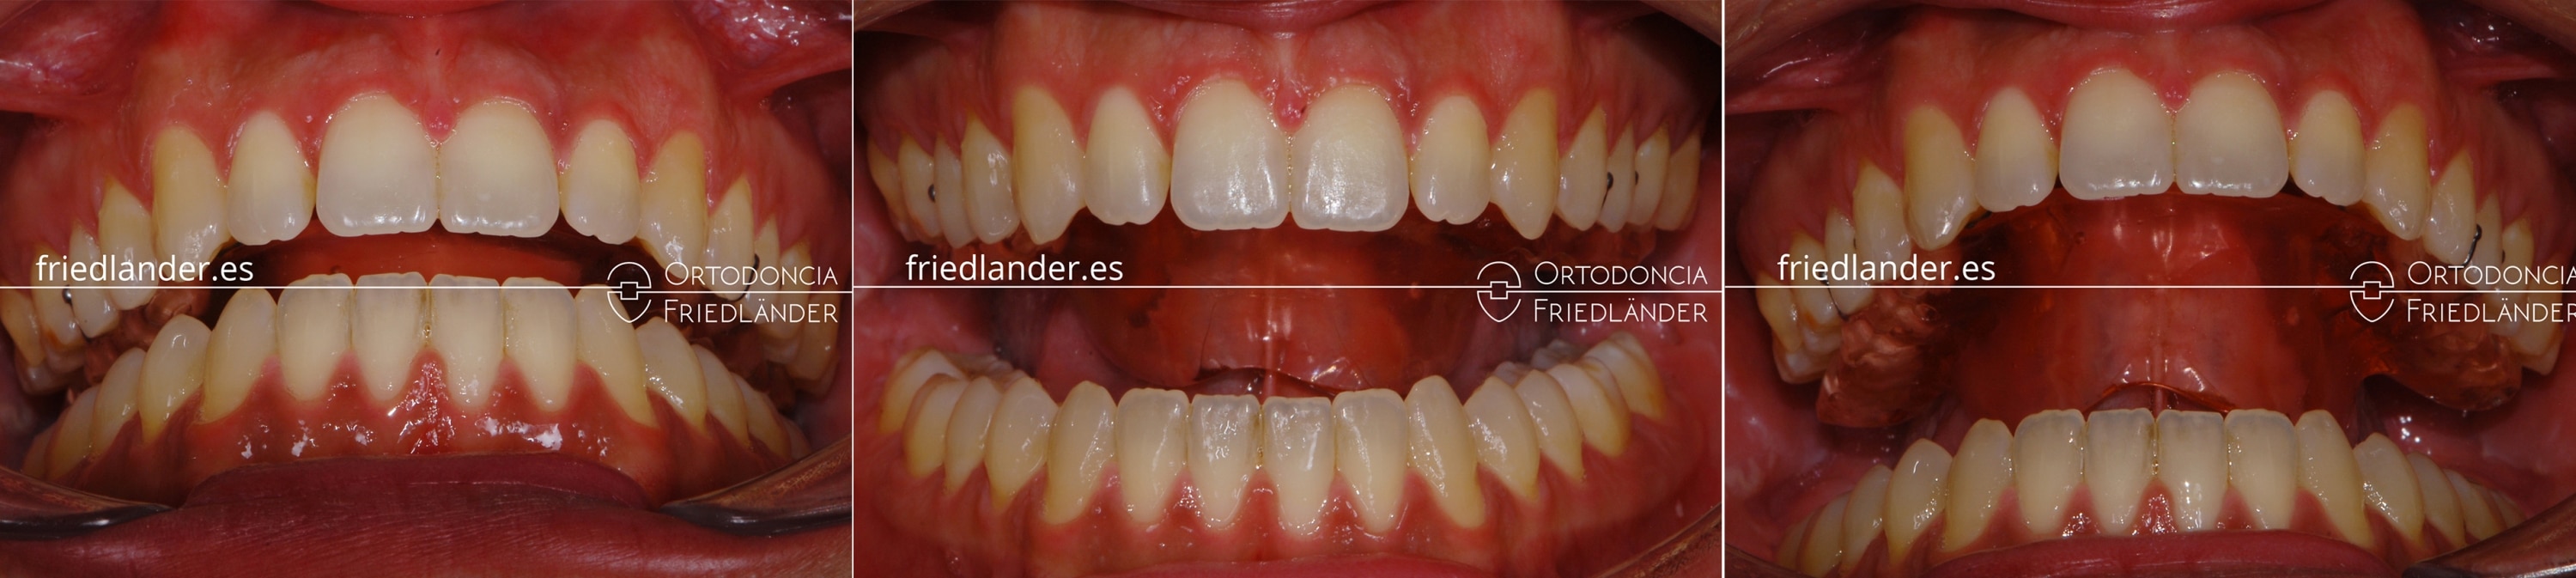

Después de unos 16 meses de tratamiento con brackets convencionales obtuvimos estos resultados

Resultados después de 16 meses con ortodocnia fija y microtornillos

Comparación del antes y después del tratamiento

Antes y después del tratamiento

Para terminar, podemos decir que hemos conseguido los objetivos deseados a nivel dental y el paciente nos comenta que está mordiendo de una manera más cómoda y está libre de dolor de la articulación.